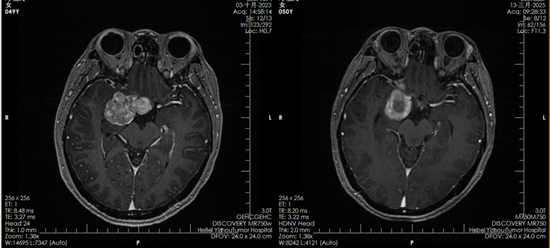

2023年10月,邓女士正式开始质子治疗。一个多月里,她接受了30次治疗。“治疗的时候一点感觉都没有,就像躺下来休息一会儿。要不是看到复查影像里的肿瘤变化,我都不敢相信这是真的。”邓女士说。

质子治疗前后对比影像

如今,复查影像显示肿瘤已被有效控制,她的坚持终于换来了可喜的结果。